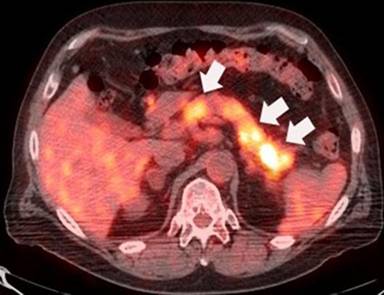

f) Pancreatic Metastasis from Melanoma

Melanoma is the sixth most common cancer in the United States. The incidence has tripled in the white population in the last 20 years. The most common metastatic sites are lungs, lymph nodes, gastrointestinal tract, brain, and bone (Figure 14). Pancreatic metastases occur in less than 5% of patients with distant metastatic sites (Figure 14). Current evidence supports using PET/CT in staging, restaging, and monitoring therapy for stage III and IV because of superior accuracy of PET/CT compared to CT alone in detecting distant metastases [13]. Early detection of metastases is crucial for patients with stage IV melanoma because, in selected cases, metastasectomy can improve the 5-year survival rate (20 months vs. 8 months).

|

Figure 14. a. Coronal PET maximum intensity projection image shows metastases of melanoma to the head of the pancreas (large arrow), right axilla, lower thoracic spine, right mesentery and left rib (small arrows). b. Coronal fused PET/CT image of another patient with melanoma metastasizing to the pancreas (arrow). |